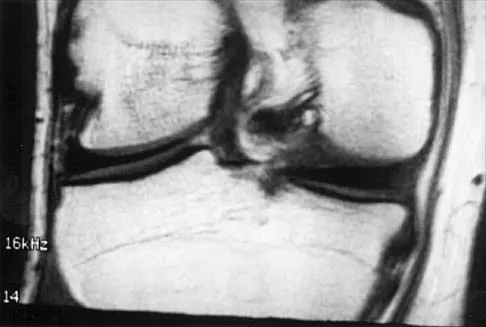

A 26-year-old man has recurrent right knee pain. Figures 9a and 9b show consecutive sagittal T2-weighted MRI scans, and Figure 9c shows a coronal T1-weighted MRI scan. What is the most likely diagnosis?

Explanation